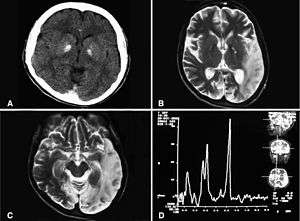

Basal ganglia calcification, cerebellar atrophy, increased lactate; a CT image of a person diagnosed with MELAS